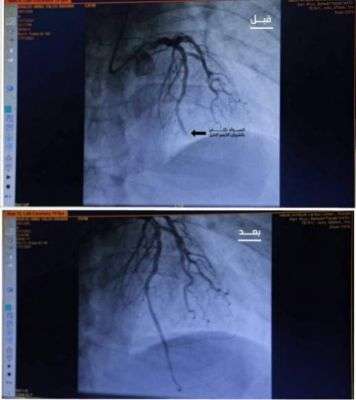

أنقذ فريق مركز الملك سلمان للإغاثة والأعمال الإنسانية الطبي التطوعي حياة مريض يبلغ من العمر 55 عامًا يُعاني من جلطة في جدار عضلة القلب نتيجة إصابته بانسداد كلي في الشريان الأيسر الرئيسي الذي يغذي 70% من عضلة القلب، وذلك بعد إجراء الفريق الطبي عملية قسطرة دقيقة له دون اللجوء للتدخل الجراحي، بالتعاون مع مركز نبض السعودية التطوعي لأمراض وجراحة القلب.

يذكر أن الفريق الطبي استقبل المريض في وقت متأخر من الليل وقام على الفور بعمل كامل الفحوصات الطبية اللازمة له وإجراء عملية استكشافية، قرر في أثرها فتح الشريان المسدود باستخدام القسطرة المذيبة للجلطات والتي تعد من أحدث الطرق لعلاج الجلطات دون جراحة.